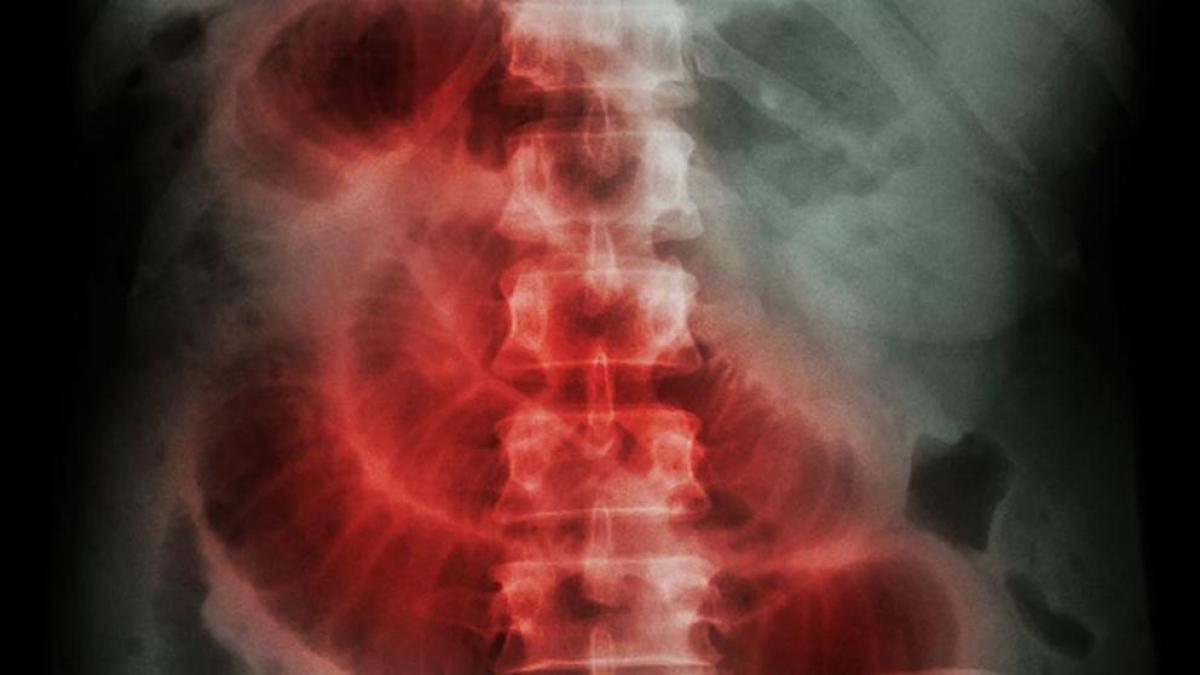

En pacientes con obstrucción del intestino delgado por enfermedad maligna intraabdominal o retroperitoneal se comparó un enfoque de tratamiento quirúrgico con uno no quirúrgico, observando que no modificó la evolución clínica durante los tres meses siguientes. Estos hallazgos deben informar las decisiones de tratamiento para pacientes hospitalizados con obstrucción intestinal maligna. The Lancet Gastroenterology & Hepatology, 1º de agosto de 2023.